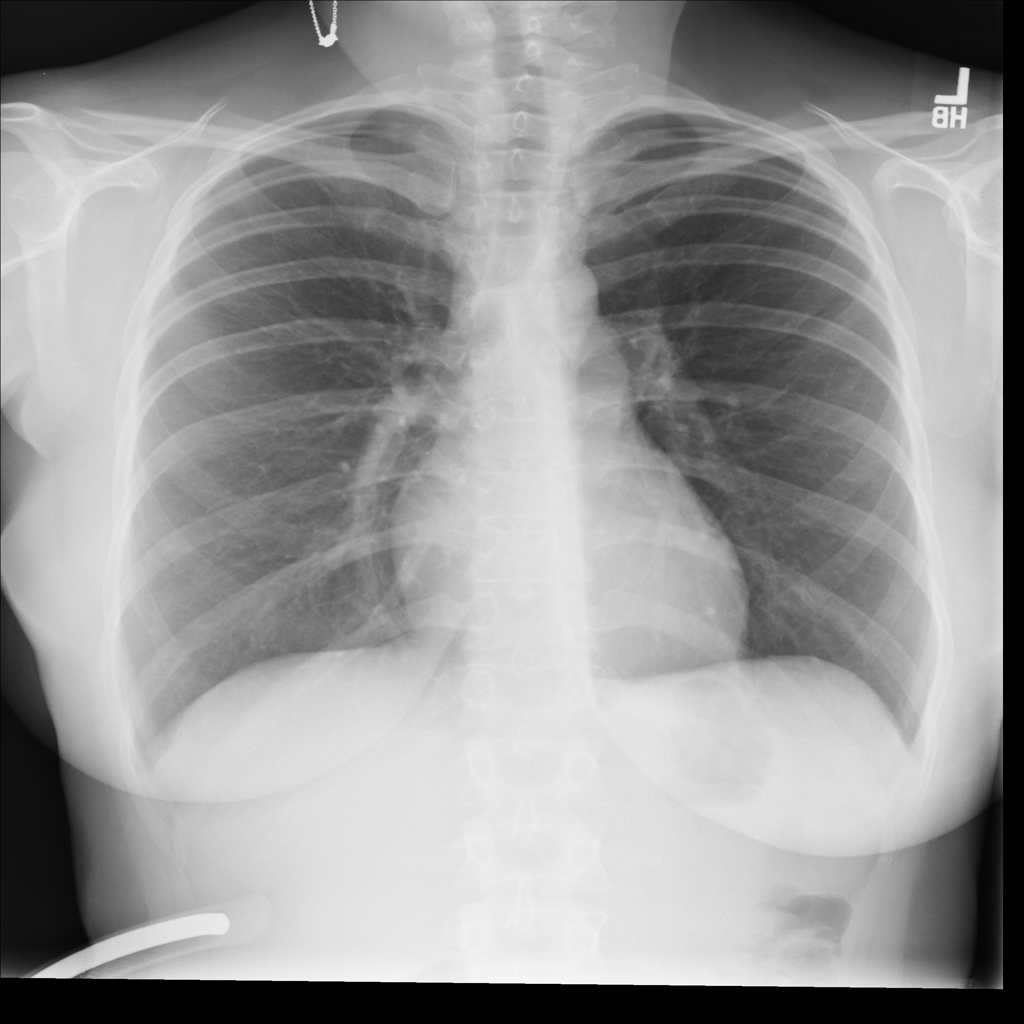

NIH Chest X-Ray dataset (Wang et al., 2017) is a large-scale medical imaging dataset comprised of 112120 X-ray images from 30805 patients. Figure 2 shows a few sample X-Ray images from the dataset. The X-ray images come labeled with up to 14 diseases and “No finding” by natural language processing (NLP) models based on the original radiological reports of each X-ray. We only select samples with “No Findings” and disease “Effusion” for the scope of our experiments. We use “Effusion” as the target label, and “Patient gender” as the sensitive attribute. After removing entries filled with N/A and abnormal values, we have a dataset with 73669 samples, and 13316 (18.1%) are labeled “Effusion”. In addition, we resized each image into size (256 * 256 * 3) with 3 channels both for computational reasons and the requirement for using pre-trained models during the training process (to be discussed in Section 6). Images are also normalized using the required mean and standard deviation based on the pre-trained model used in the experiments (Sandler et al., 2019). Detailed statistics of NIH Chest X-Ray are in Table 4.

EffusionEffusion

Total 1 0 Total

gendergender

1 7434 (10.1%) 33916 (46.0%) 41350 (56.1%56.1\%)

0 5882 (8.0%) 26437 (35.9%) 32319 (43.9%)

Total 13316 (18.1%18.1\%) 60353 (81.9%81.9\%) 73669 (100.0%)

Table 4. Statistics for NIH-Chest X-Ray dataset. EffusionEffusion is used as target label and gendergender as sensitive attribute.

Refer to caption

Figure 2. Four sample Chest X-ray images from NIH Chest X-Ray dataset.